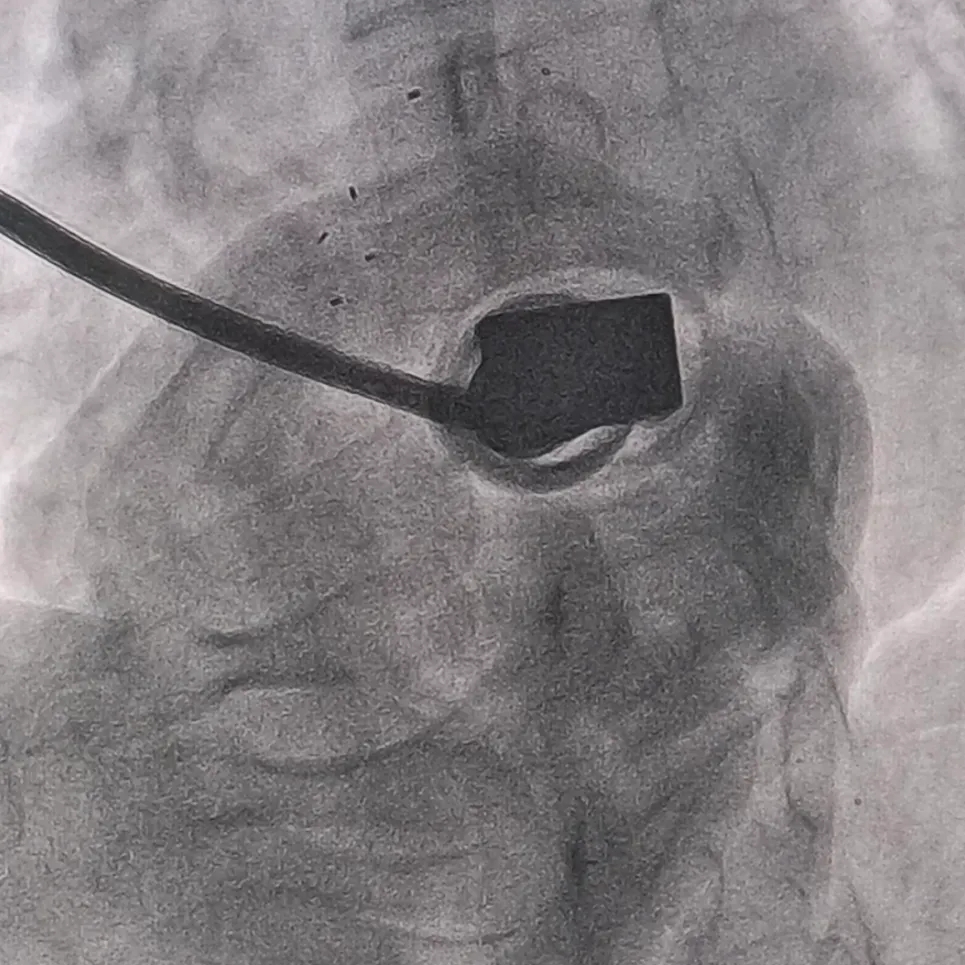

DSA下推出前4个显影点,展开左盘

左盘展开后,轻拉成型线使盘面成型,再将输送系统整体后撤贴靠房间隔

封堵器锁定成型后,牵拉试验可见5个显影点整体随钢缆移动,右盘显影点未发生明显位移

5个显影点排列聚拢